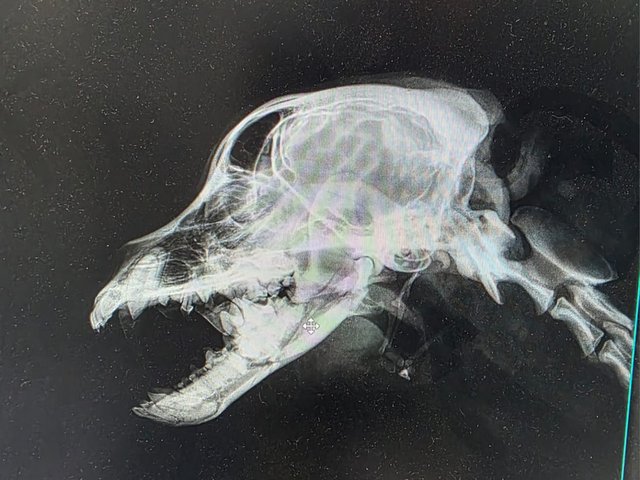

Röntgenbilder zeigten das Ausmaß der Zerstörung des Unterkiefers und den Bruch eines Beines.

Dieser Hund muss grausame Schmerzen haben, Zähne sind aus der Verankerung gerissen und sein Gesichtsschädel ist nicht mehr symmetrisch. Ein großes Stück des Unterkiefers ist komplett abgebrochen.

Camush Kopf ist wieder symmetrisch, der Kiefer wird jetzt mit Platte und Verdrahtung zusammengehalten und ein paar Zähne fehlen jetzt.